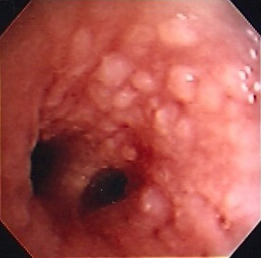

Tracheal-bronchial papillomatosis

From the collections of Jose Fernando Santacruz MD, FCCP, DAABIP and Erik Folch MD, MSc; used with permission